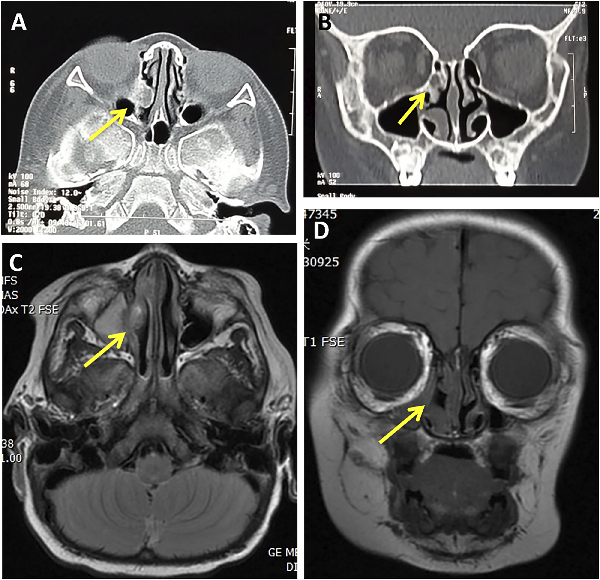

Currently, there is no evidence of recurrence after 1 year since the operation (Figure 3).

Figure 3

The patient’s CT (A, B) and MRI (C, D) of paranasal sinuses after operation: The yellow arrows show the changes in the operative area 1 year after operation: no tumor recurrence, a small amount of local hyperosteogeny and mucosal thickening.